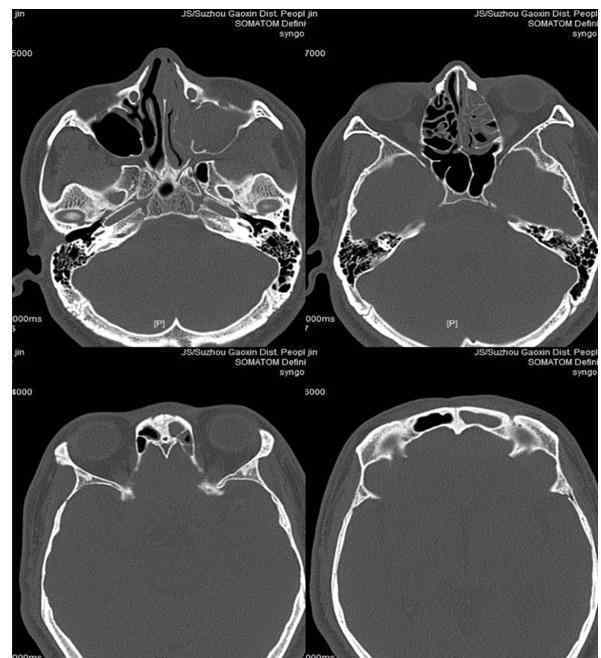

图1鼻窦CT显示左鼻塞、左上颌窦、筛窦和额窦炎

由于多年反复头痛,李先生在医院外的许多方面都没有改善用药。十天前,我来到苏州高新区人民医院耳鼻喉科体检。耳鼻喉科主任王新教授询问了他的病史。患者描述头痛在左前额,伴有鼻塞和流鼻涕。通过鼻内镜和鼻窦CT检查,发现程老师鼻中隔左侧弯曲,左侧上颌窦、筛窦、额窦因梗阻引起鼻窦炎。教授用鼻内镜手术治疗李先生。手术后,他的鼻腔通畅。鼻窦炎治愈后,多年的头痛消失了。出院后,李先生愉快地发来横幅,向医护人员表示诚挚的感谢。